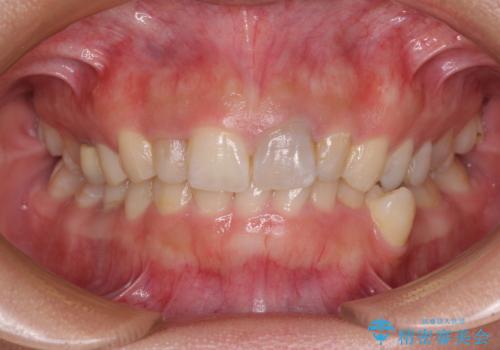

歯列から飛び出た歯 ワイヤー矯正で整った歯列に

- 下顎の歯列から飛び出した小臼歯を気にして来院された患者様です。

歯列以外に、上顎左右側切歯が矮小歯であり、上顎4前歯は失活していたため、矯正治療で歯列を整えるとともに上顎前歯の幅を調整し、矯正治療後にオールセラミッククラウンにて審美歯科治療を行うこととしました。

矯正治療は、小臼歯1本分を歯列に納めないいけない状態であったため、表側のワイヤー装置にて行うこととしました。